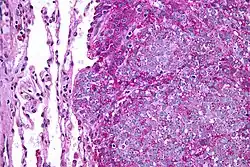

| Micrograph of metastatic Ewing sarcoma (right of image) in normal lung (left of image). PAS stain. | |

Ewing sarcoma is a small-blue-round-cell tumor that typically has a clear cytoplasm on H&E staining, due to glycogen. The presence of the glycogen can be demonstrated with positive PAS staining and negative PAS diastase staining. The characteristic immunostain is CD99, which diffusely marks the cell membrane. However, as CD99 is not specific for Ewing sarcoma, several auxiliary immunohistochemical markers can be employed to support the histological diagnosis.[23] Morphologic and immunohistochemical findings are corroborated with an associated chromosomal translocation, of which several occur. The most common translocation, present in about 90% of Ewing sarcoma cases, is t(11;22)(q24;q12),[24][25] which generates an aberrant transcription factor through fusion of the EWSR1 gene with the FLI1 gene.[26]